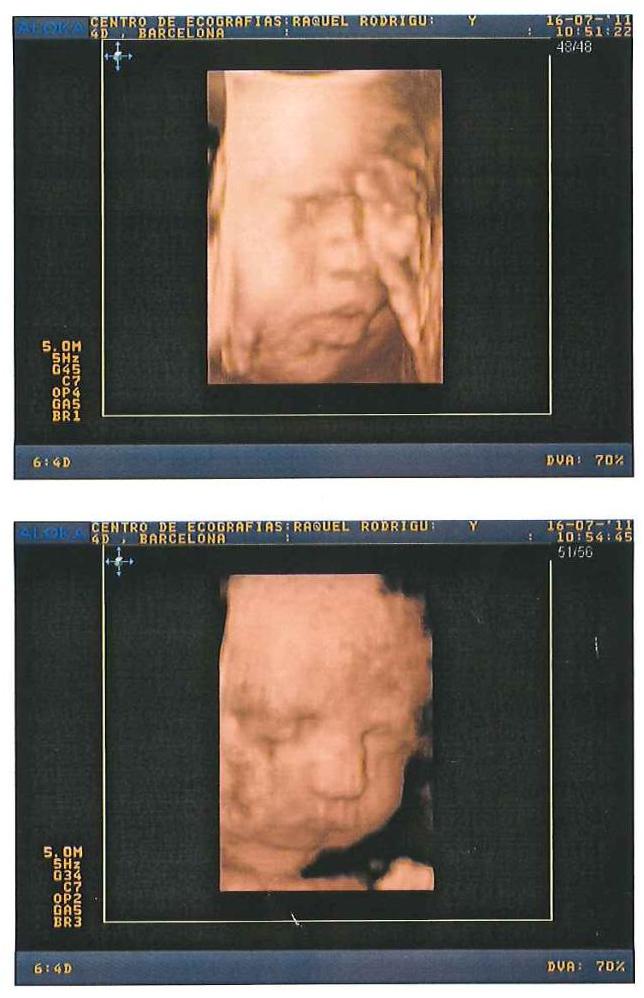

Cumplidos ya los 7 meses de embarazo, por fin le hemos podido ver la carita, aunque de manera «virtual», a nuestro futuro hijo. Qué poquito queda…